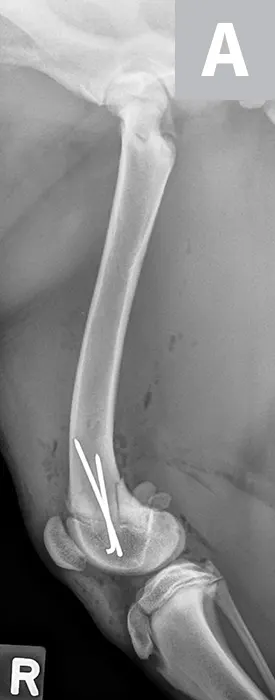

Maggie was managed overnight with analgesia (ie, hydromorphone [0.05 mg/kg IV q4-6h]) and nursing care. The following morning, Maggie was placed under general anesthesia and given a morphine epidural, and surgical fixation of the fracture was performed through a craniolateral approach to the stifle. The distal femoral physis is W-shaped and has inherent stability when reduced; however, additional stabilization is required to provide adequate resistance to the forces applied across the fracture and to allow for the stability needed for healing. Two smooth pins were placed obliquely across the fracture site (Figure 2). The pins should cross proximal to the fracture site to provide maximal repair stability.7

Figure 2

Lateral (A) and craniocaudal (B) radiographs of the femur immediately after open reduction and internal fixation with 2 cross pins. The pins cross proximal to the fracture site, which is important for stability of the repair.